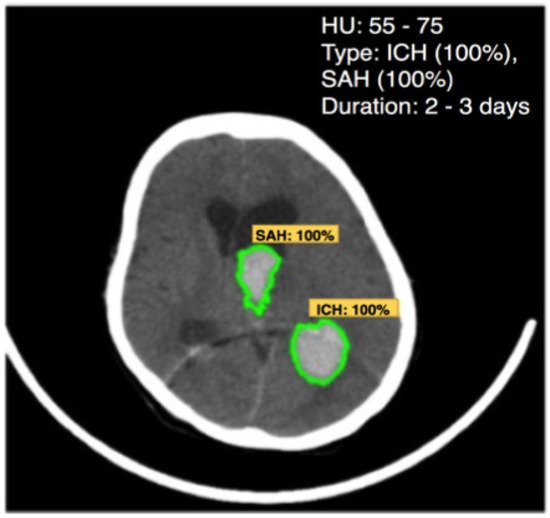

The machine-learning algorithms used in the knowledge layer are decision trees and deep neural networks. Decision trees have been successfully used in a wide range of fields such as speech recognition, remote sensing, and medical diagnosis. The reason for choosing a decision tree at the knowledge layer here is that the patient records for hypertension are all in text format. The decision tree uses input data to learn and generate knowledge with the same rules as to how humans think. It breaks down a complex decision-making process into simple rules that are simple to understand and suitable to use for datasets of diverse attributes and data types. Deep learning with Faster R-CNN Inception ResNet v2 is another machine-learning algorithm to be used in the knowledge layer for brain hemorrhage diagnosis. Deep-learning techniques have been successfully applied in a wide range of fields, especially in medical images analysis.

| Matter | Density (HU) |

|---|---|

| Air | −1000 |

| Water | 0 |

| White matter | 20 |

| Gray matter | 35–40 |

| Hematoma | 40–90 |

| Bone | 1000 |